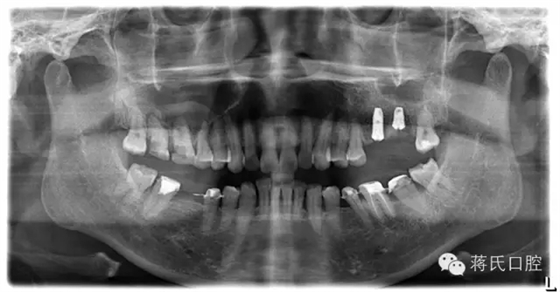

8.種植后全景片